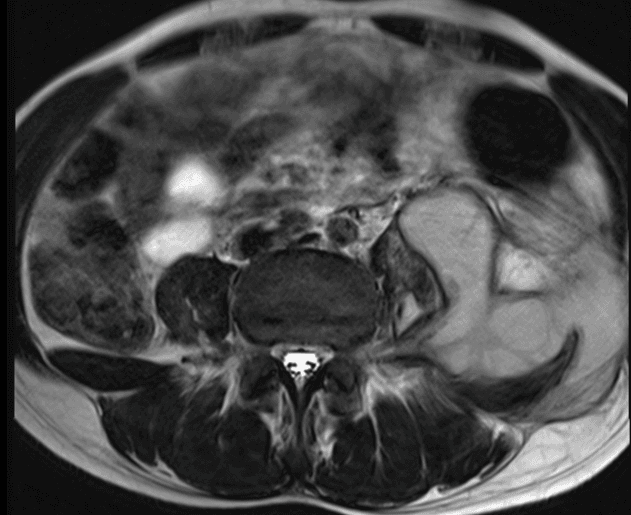

Figura 2.